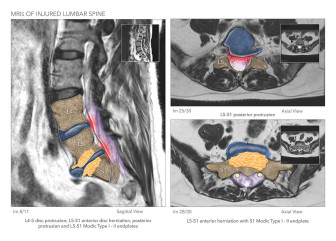

Lumbar Radiculopathy and Epidural Steroid Injections